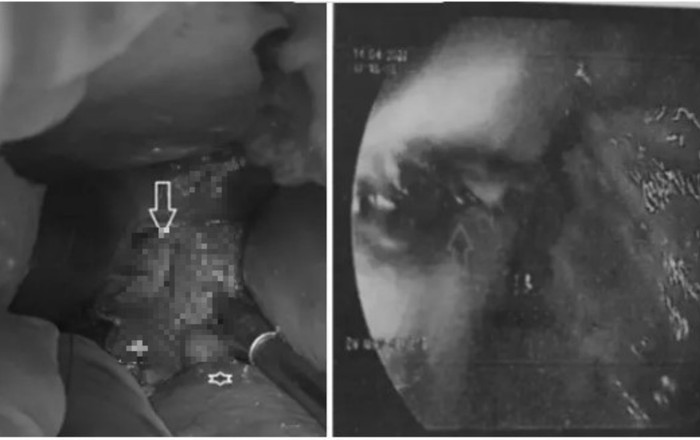

Hình ảnh thực quản trong nội soi dạ dày (bên phải) và lỗ thủng thực quản. (Ảnh: Vietnamnet).

Bệnh nhân tiếp tục được chuyển lên khoa Ngoại tổng quát để theo dõi và làm thêm các xét nghiệm cần thiết. Kết quả nội soi dạ dày cho thấy bị rách tâm vị thực quản dưới nham nhở, diện rách rộng, gồ cao, đáy sâu chưa loại trừ thủng bít.

Kiểm tra vùng thực quản, các bác sĩ phát hiện đường rách dài 3cm. Người bệnh được phẫu thuật khâu lại lỗ thủng thực quản, đắp một phần mạc nối lớn lên đường khâu.